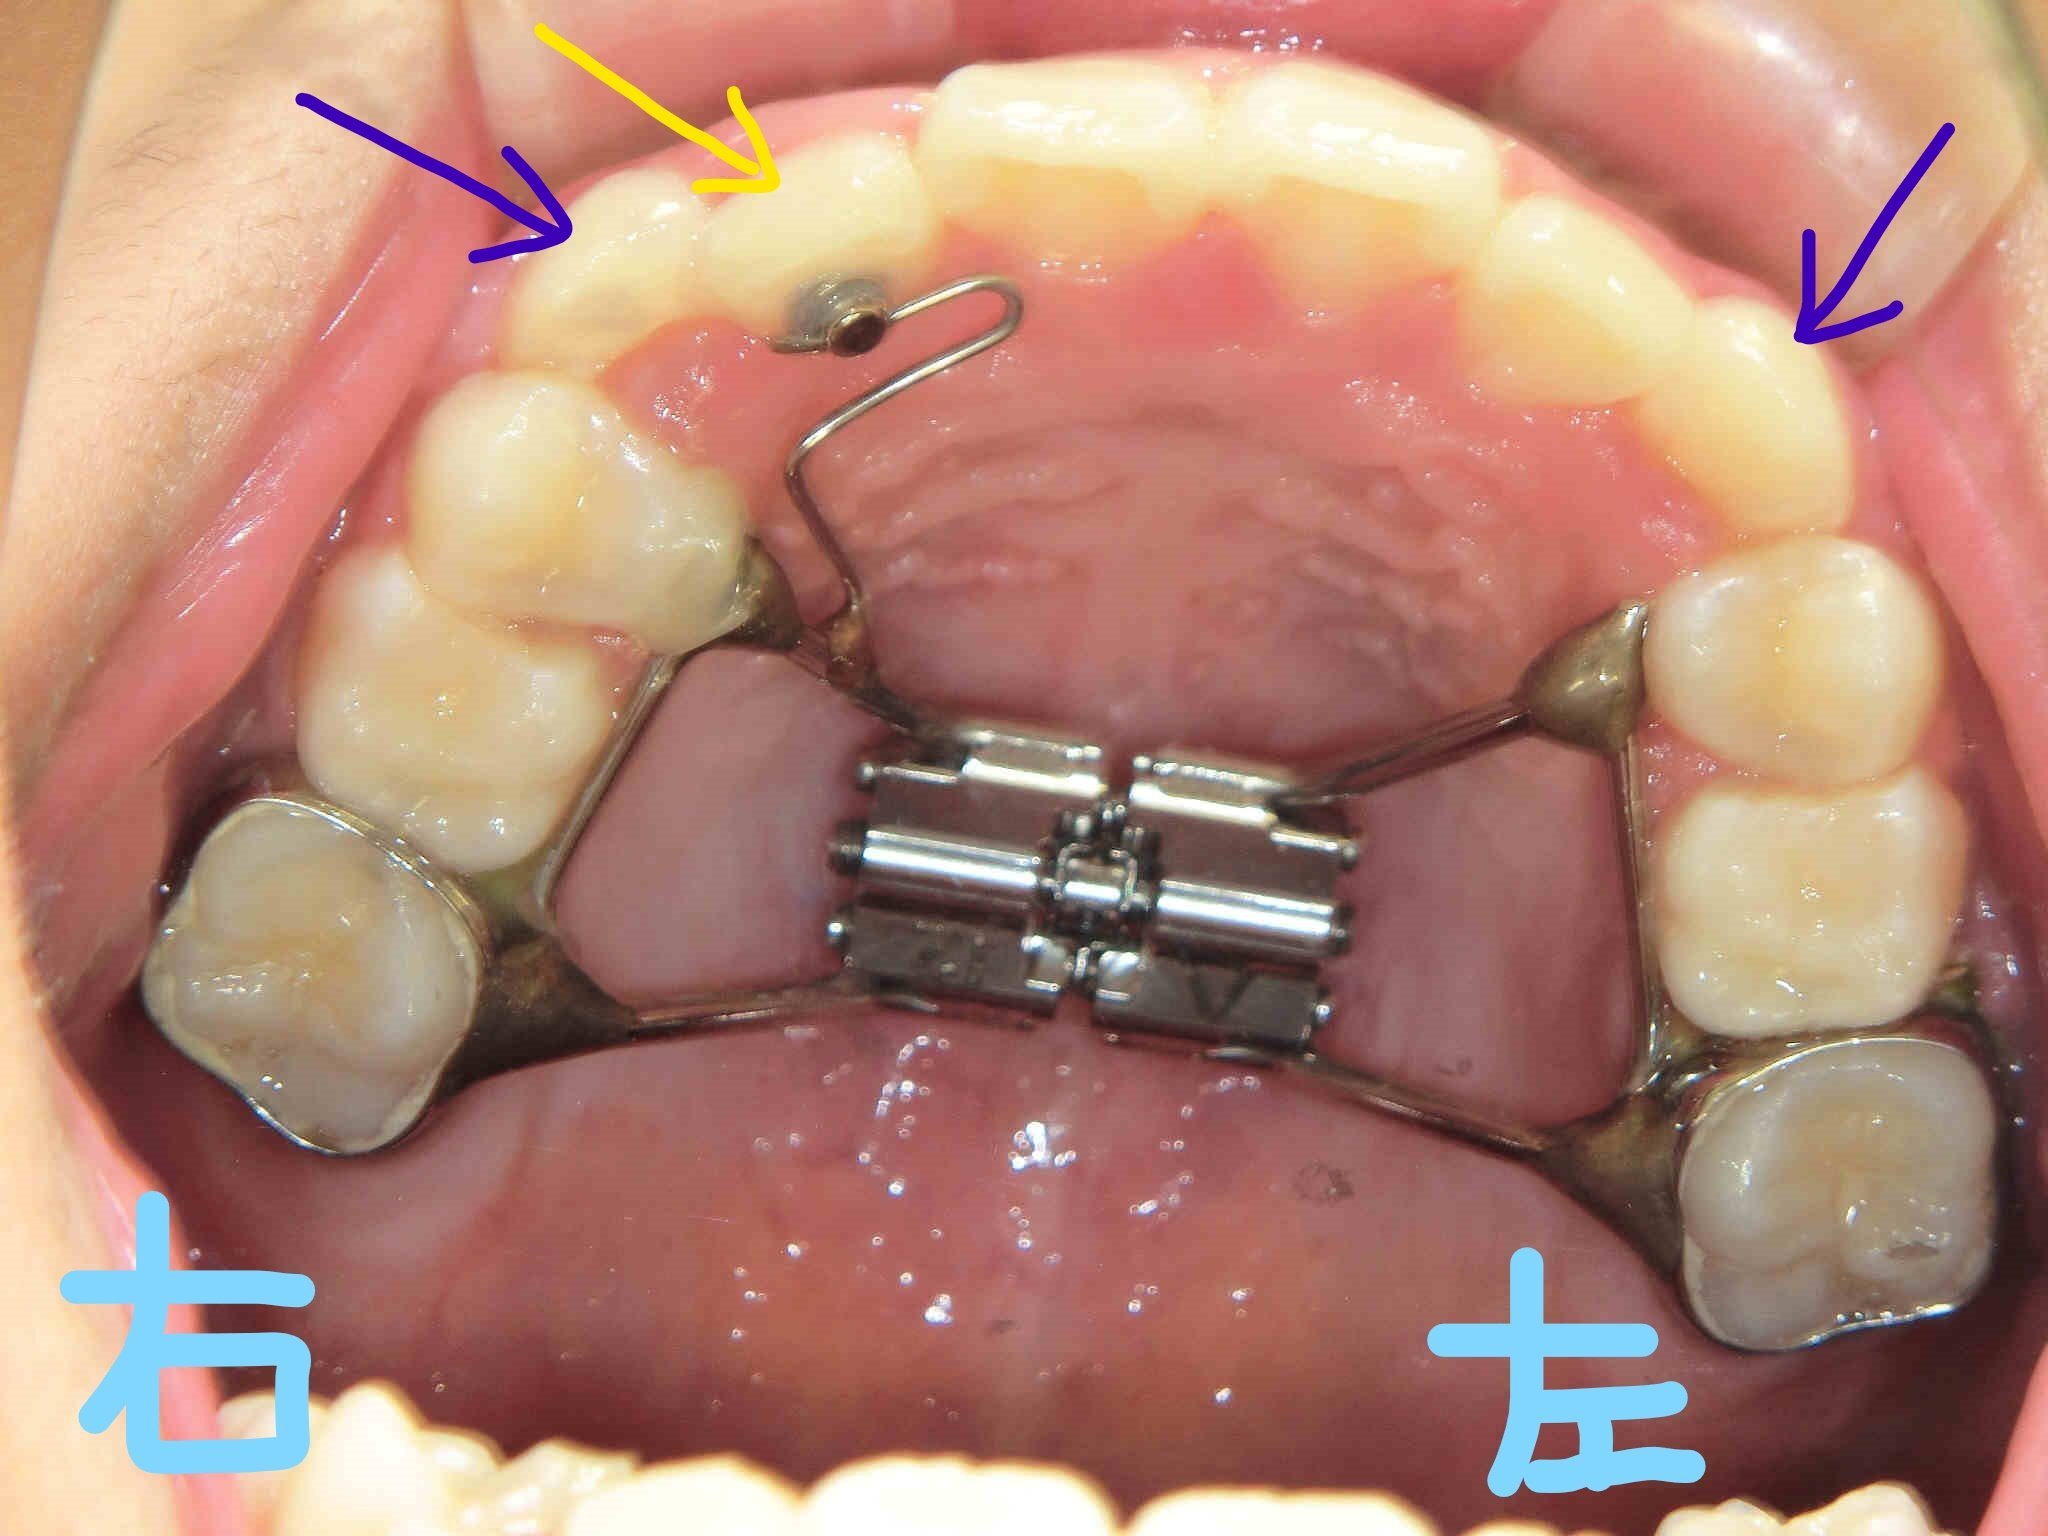

続く写真では、左上が上顎を下から見たもの、右上が下顎を上から見たものです。固定式拡大装置の装着により、前歯の誘導と歯列拡大を図ることを目的としています。

固定式装置は見た目にやや存在感がありますが、装着による痛みは個人差があり、多くのケースで大きな痛みを感じることは少ないとされています。